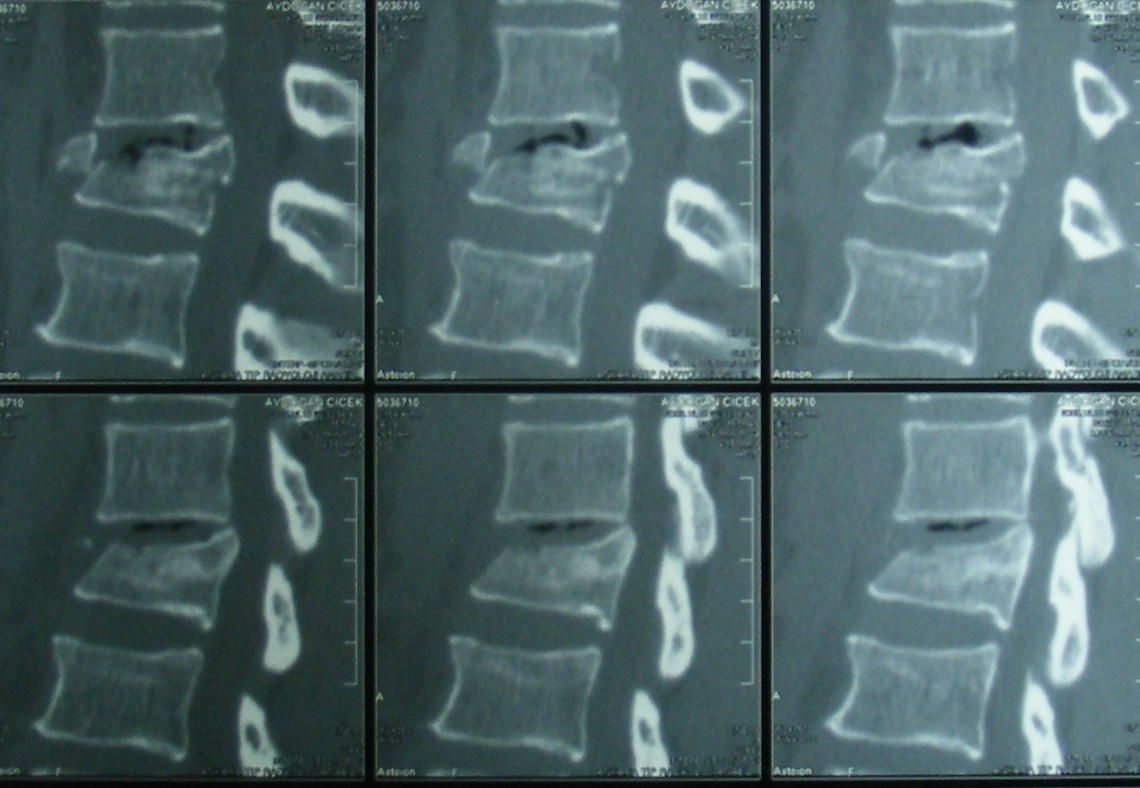

Omurga Kırığı

Omurga kırıkları osteoporozun olmadığı sağlıklı kişilerde trafik kazası ya da yüksekten düşme gibi yüksek enerjili travmalar sonucu oluşur. Eğer omurilik basısına neden olursa kısmi ya da tam felç ile sonuçlanabilir.

Eğer travma ilerleyen dönemde deformiteye yol açmayacaksa veya sinirlere baskı yaparak nörolojik bulguya neden olmadıysa korse ile tedavi edilebilir. Bu amaçla sert polietilen korseler ya da metalden yapılmış çerçeve tipi korseler kullanılabilir. Omurganın ağır zarar gördüğü durumlarda ileride oluşabilecek deformiteyi engellemek için omurganın vida ve çubuklarla sabitlenmesi gerekebilir. Nörolojik bulgu oluşturan bir kemiksel bası varsa, aynı seansta bu bası da ortadan kaldırılabilir.